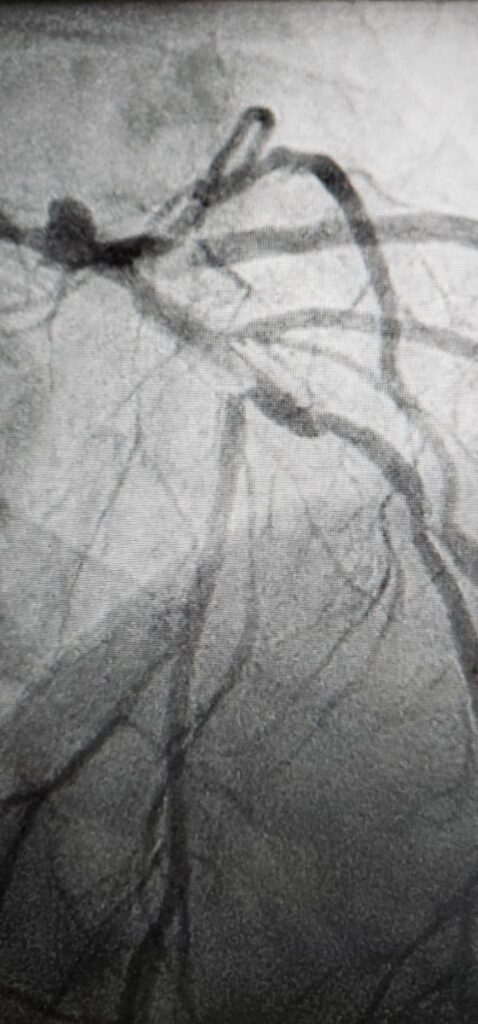

Rotoblācijas angioplastija ir paredzēta pacientiem ar smagiem pārkaļķotiem sirds asinsvadu bojājumiem, kad tradicionālās ārstēšanas metodes vairs nav pietiekami efektīvas vai drošas. LRS invazīvie kardiologi Nikolajs Sorokins un Valters Stirna skaidro, ka aterosklerozes process bieži noved pie asinsvadu sieniņu pārkaļķošanās, veidojot cietus kā “mūris” kalcija sāļu “stalaktītus”. Šādos gadījumos ar balonu paplašināšana ir neiespējama vai bīstama.

Rotoblācijas metodes princips ir mehāniski noārdīt šos cietos kalcija nogulsnējumus. Artērijā tiek ievadīts speciāls urbis, kas, griežoties ar lielu ātrumu, izveido “tuneli”, atbrīvojot asinsvadu. Pēc cietā slāņa noņemšanas un asinsvada elastīguma atjaunošanas, procedūru var turpināt ar balona paplašināšanu, bieži vien kombinējot ar ultraskaņas litotripsiju (kalcija šķelšanu ar ultraskaņu), un stenta implantāciju.

Galvenā rotoblācijas priekšrocība ir spēja efektīvi sagatavot artēriju stenta implantācijai, kas samazina komplikāciju risku un novērš asinsvada atkārtotu sašaurināšanos ilgtermiņā.